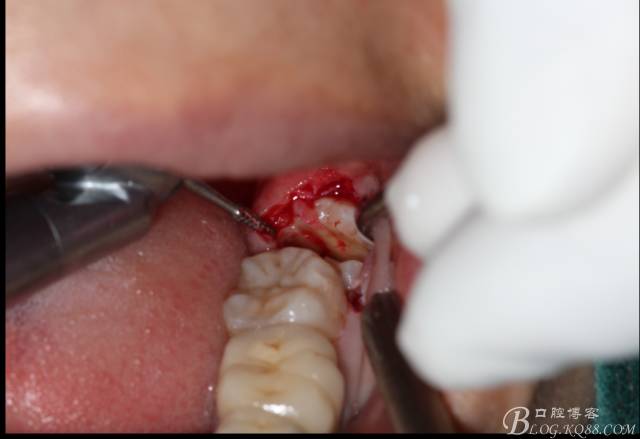

角度鍋輪機(jī)結(jié)合冷鹽水冷卻分冠

分冠完成